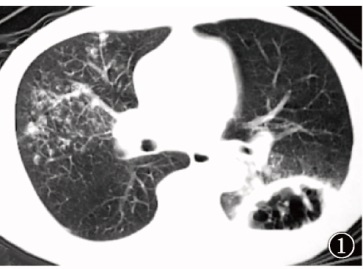

图4~9

图4~9肺结核与肺癌共病的影像学表现。 图4~6为同一患者,既往肺结核病史;图4可见患者右肺上叶后端残留支气管扩张;图5显示患者7个月后支气管扩张区呈黏液嵌塞征表现,周围散在结节影;图6显示患者13个月后支气管扩张的管腔内软组织病变生长呈典型支气管铸型征表现;行支气管镜组织活检,病理诊断为鳞癌;同时,气道分泌物抗酸杆菌涂片阳性,提示结核病复发。图7~9为同一患者,诊断为左上叶活动性肺结核,涂阳,初治。图7为患者治疗前,右肺中间段支气管未见明显异常;图8为患者经抗结核治疗后病变逐渐吸收,但右肺中间段支气管略见狭窄,未采取措施;图9为患者抗结核治疗5个月后复查CT,可见肺结核病变显著吸收,中间段支气管管壁狭窄直至闭塞,不符合结核病转归病程,呈“矛盾现象”;支气管镜活检病理诊断为鳞癌。